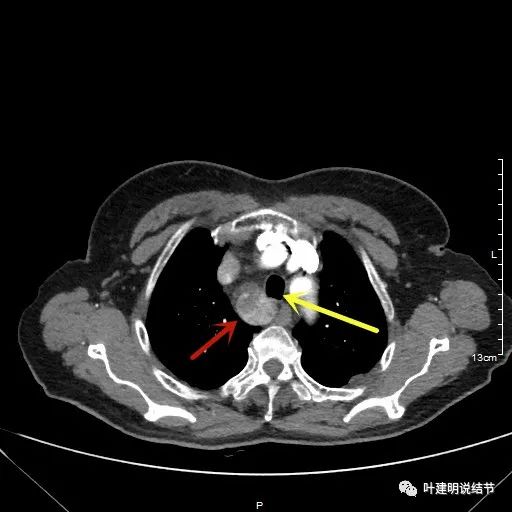

金华地区的某A,今年已经76岁了,近段时间觉得胸闷不适,还有刺激性咳嗽,总是不会好,到当地医院查了胸部CT,发现是纵隔肿瘤。当地医生建议她到金华市中心医院做下气管镜下穿刺活检,以明确肿瘤性质。因为认识我们医院的某外科主任,所以又建议她来找我,结果我一看她从当地带来的片子,是纵隔内巨大的占位,与气管关系密切,位于气管右侧、食管右前侧、上腔静脉左侧、无名静脉后侧,被诸多结构包绕着,而且肿瘤密度不均,靠气管与无名静脉侧间隙不清,首先考虑纵隔内恶性或交界性肿瘤,由于年纪这么大,手术风险较高,若与气管有侵犯,则手术达不到根治,我也觉得应该先行经气管镜下的穿刺活检,明确病理后再考虑怎么办。所以让某A住到呼吸内科去,打算行气管镜下纵隔肿瘤穿刺活检。因当地的片子扫到胸顶部为止,没有做增强,我们先取本院增强片子上达胸顶,下达肿瘤下缘的范围来看看肿瘤的样子:

胸顶就开始有肿瘤了,黄色示受压迫移位的气管,红色示肿瘤